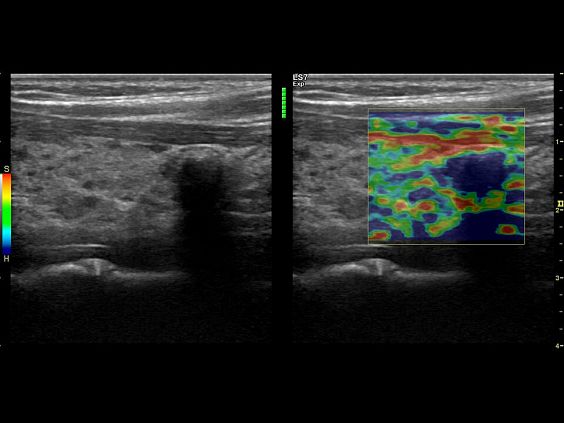

Клинические изображения

Logiq S7 XDclear — УЗИ аппарат нового поколения, который обеспечивает простой и комфортный рабочий процесс, высокую производительность и предлагает широкий набор современных инструментов для проведения уверенной диагностики. Его расширенный функционал включает такие возможности как B-Flow — недопплеровская технология отображения кровотока в B-режиме, компрессионная эластография (качественная и полуколичественная), количественный анализ васкуляризации, функцию В-Steer+ — изменение угла наклона УЗ луча в B-режиме, 3D/4D диагностику и мультимодальную визуализацию.

- Elastography Imaging - режим эластографии. Поддерживается датчиками C1-6-D,C1-5-D, 9L-D, L3-12-D, ML6-15-D, 11L-D, IC5-9-D, BE9CS, BE9CS-D.

- Q-analysis Option for Elastography and CF/PDI Quantification - программа количественного анализа для эластографии и анализа васкуляризации в режиме ЦДК и ЭД

Ультразвуковой аппарат LOGIQ S7 XDclear предназначен для использования специалистами из различных областей диагностики. Его расширенный функционал включает такие возможности как B-Flow — недопплеровская технология отображения кровотока в B-режиме, компрессионная эластография (качественная и полуколичественная), количественный анализ васкуляризации, функцию В-Steer+ — изменение угла наклона УЗ луча в B-режиме, 3D/4D диагностику и мультимодальную визуализацию.